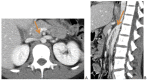

Nutcracker phenomenon is the descriptor for a patient's anatomy whenever the left renal vein becomes compressed between the abdominal aorta and the superior mesenteric artery. Nutcracker syndrome is the terminology used when the nutcracker phenomenon is accompanied by symptoms including pain (abdominal, flank, pelvic), hematuria, and orthostatic proteinuria. Diagnosis can be made with Doppler ultrasound, venography, computed tomography, or magnetic resonance imaging. This case demonstrates some of the typical findings of nutcracker syndrome. The limited clinical features and interesting imaging findings, in addition to the young age of the patient, make this a notable case.